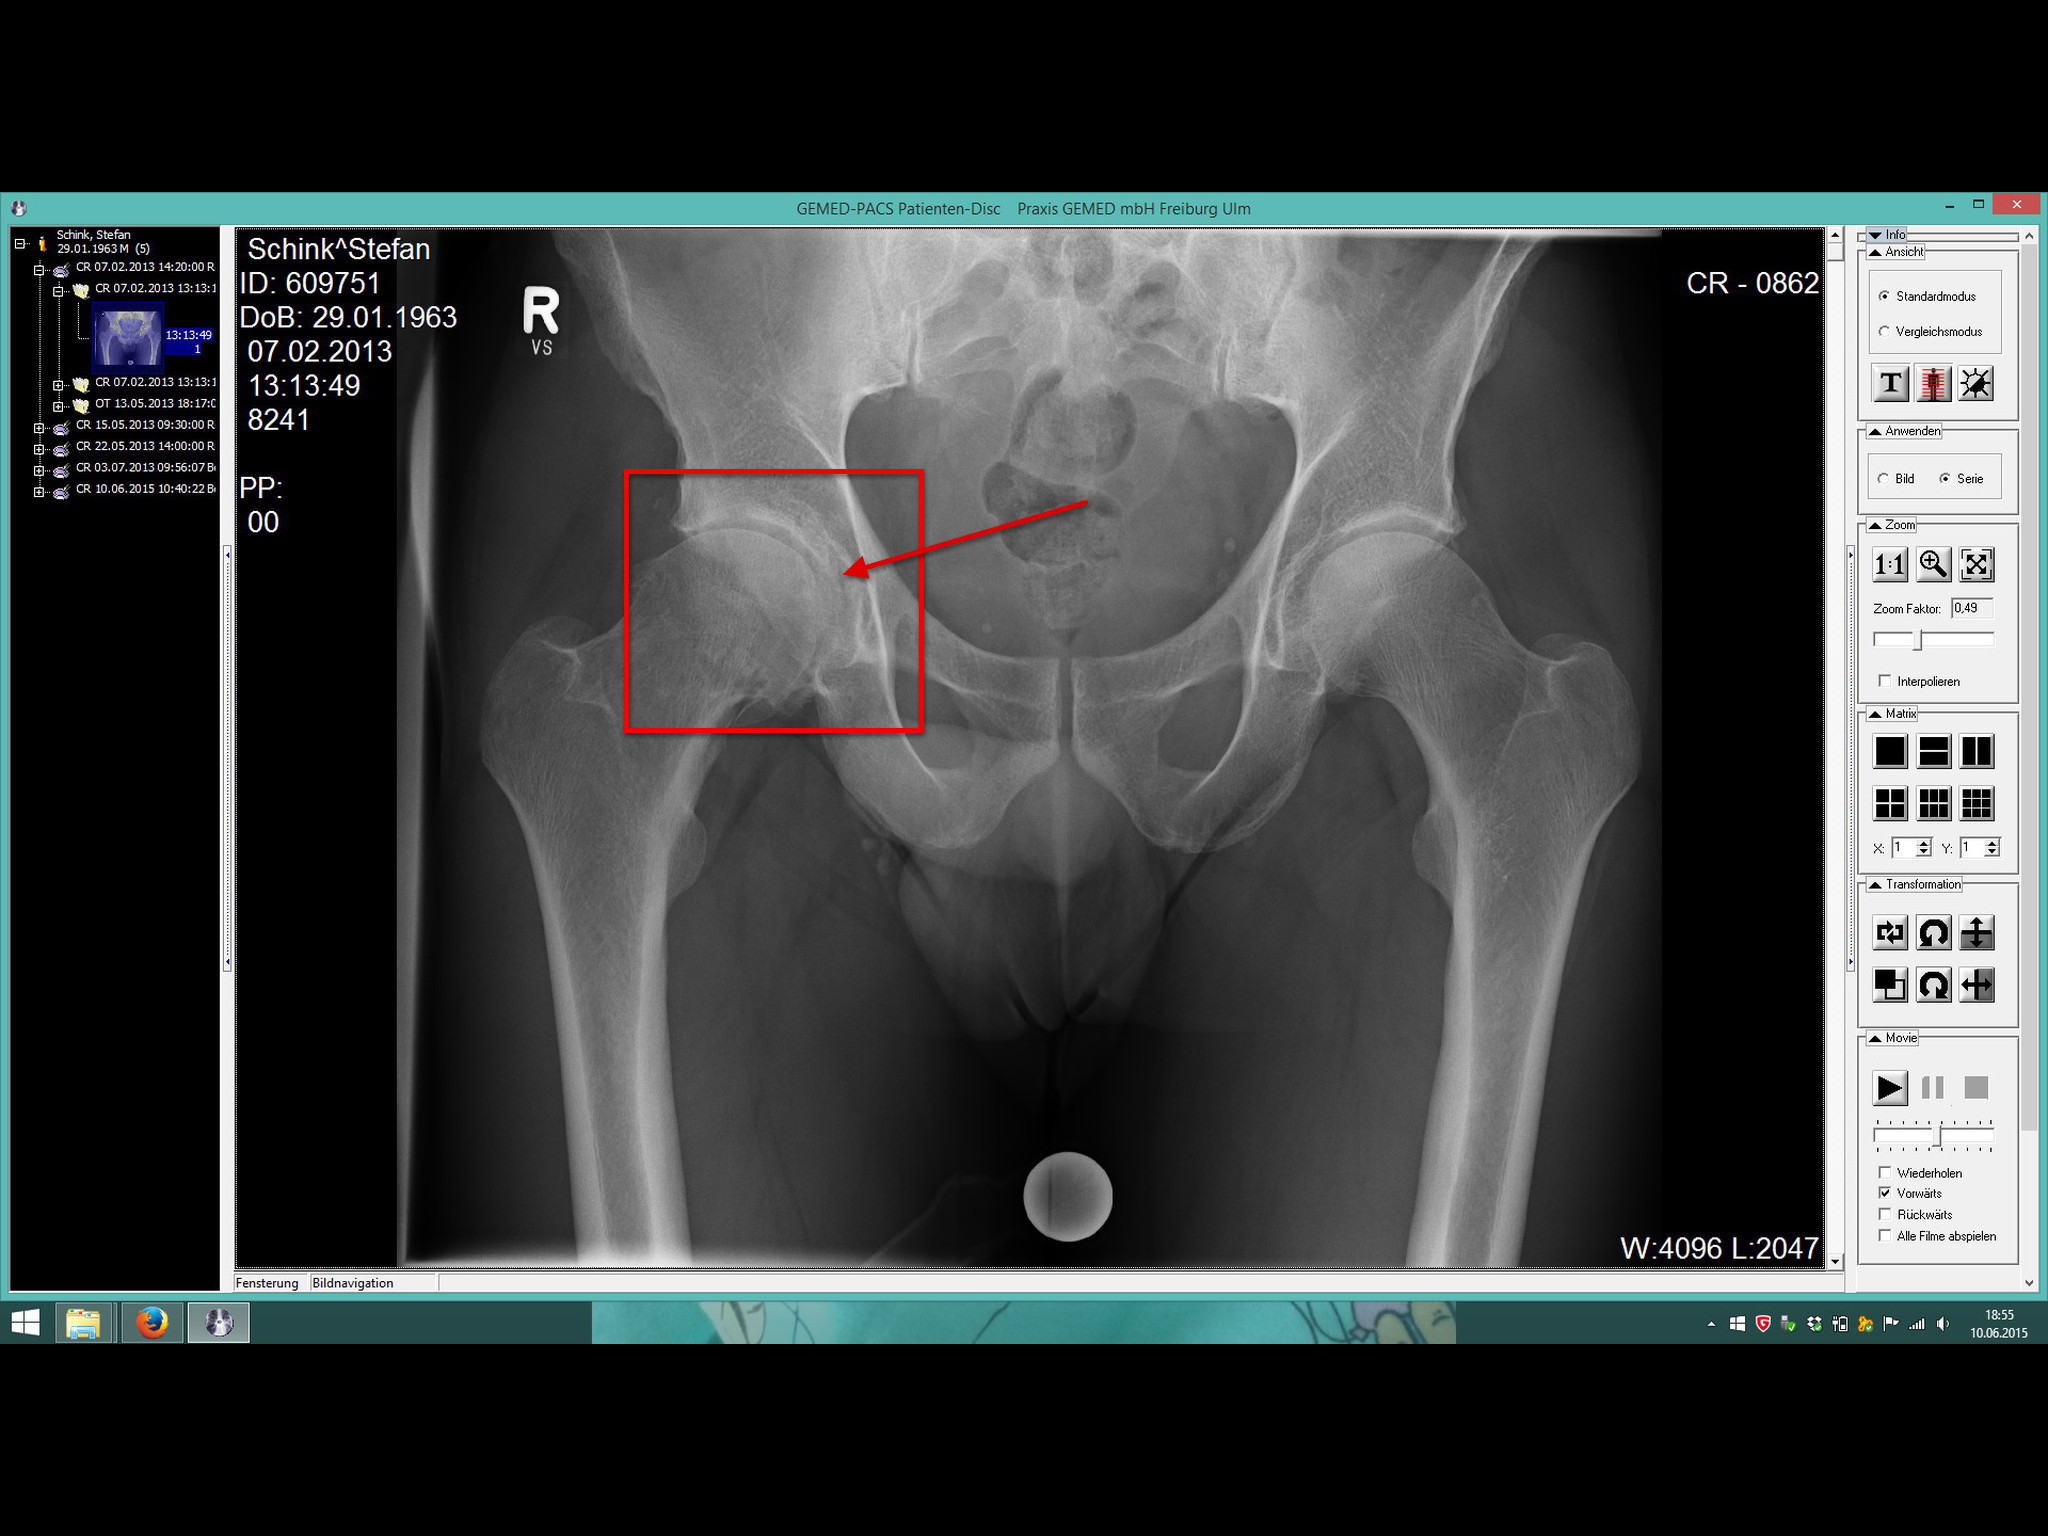

heute war TÜV-Prüfung in der orthopädischen Klinik Kassel für mich und meine nun schon zwei Jahre alte künstliche Hüfte.

Ich habe die neue Plakette anstandslos bekommen und jetzt sogar für drei Jahre (erst im Juni 2018 muss ich wieder zum Röntgen, vorrausgesetzt es passiert nichts Aussergewöhnliches). Beweglichkeitstest, Vermessung der Lage des Gelenkes und neues Röntgen waren Inhalt der TÜV-Prüfung.

Auf dem ersten Röntgenbild ist im roten Viereck gut zu erkennen, dass der weisse Strich (Knorpel) zwischen Hüftkopf und Hüftpfanne kaum noch vorhanden ist, kein Knorpel gleich sehr starke Reibung im Gelenk gleich sehr starke Schmerzen. Deswegen wurde das neue Gelenk eingesetzt und das mit sehr sehr sehr grossem Erfolg, wie ich ja in meinen letzten Beiträgen geschrieben habe.

Das andere Hüftgelenk wird auch irgendwann gewechselt werden müssen, aber im Moment ist da noch kein Handlungsbedarf, da sich der Knorpel in den letzten zwei Jahren nicht wesentlich verringert hat, wie ein Vergleich der beiden Röntgenbilder zeigt.

PS: Auf dem ersten Foto sind deutlich die Tackerkrallen zu erkennen, mit denen die Wunde nach der Op verschlossen wurde (wenn ich es noch richtig im Kopf habe, waren es 42 Krallen).